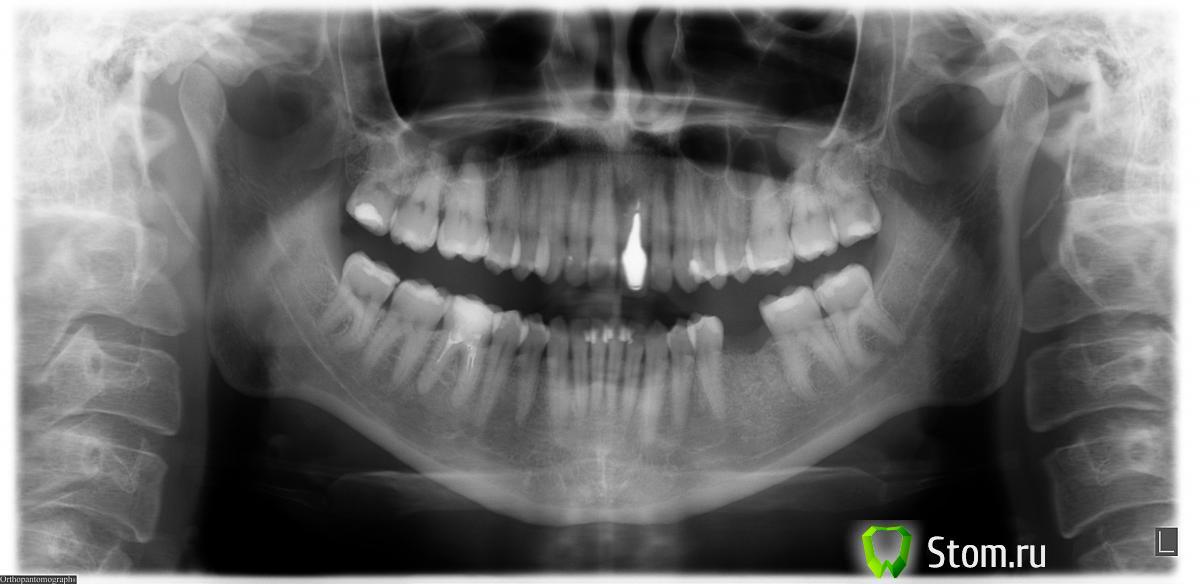

anna78 Опубликовано 13 декабря, 2011 Поделиться Опубликовано 13 декабря, 2011 (изменено) Прокомментируйте снимок, пожалуйста. Особенно волнуют места: между верхушек корней верхних 2-ки и 3-ки справа на снимке (показалось какое-то затемнение), 1-цы и 2-ки внизу околокорневое состояние. Изменено 13 декабря, 2011 пользователем anna78 Ссылка на комментарий

shishok Опубликовано 13 декабря, 2011 Поделиться Опубликовано 13 декабря, 2011 По этому снимку особых проблем не видно,точнее можно сказать по прицельному снимку.У Вас на 21 была резекция?А те зубы,про которые Вы спрашивали,беспокоят?Нужно обязательно перелечить 46 зуб. Ссылка на комментарий

anna78 Опубликовано 13 декабря, 2011 Автор Поделиться Опубликовано 13 декабря, 2011 (изменено) По этому снимку особых проблем не видно,точнее можно сказать по прицельному снимку.У Вас на 21 была резекция?А те зубы,про которые Вы спрашивали,беспокоят?Нужно обязательно перелечить 46 зуб. Спасибо за комментарий. С 21 зубом: почти 20 лет назад была резекция, 7 лет стоит коронка. Зубы не беспокоят. Выложу прицельный нижнии 1-ца и 2-ка, у врача было подозрение, что есть затемнение между корнями. 46 зуб последний раз был пролечен 11 лет назад, до сих пор не беспокоил, имеет ли смысл его сейчас трогать, т.к. пломба большая, останется ли после лечения от его коронки что-нибудь? Изменено 13 декабря, 2011 пользователем anna78 Ссылка на комментарий

Afffinity Опубликовано 14 декабря, 2011 Поделиться Опубликовано 14 декабря, 2011 имеет ли смысл его сейчас трогать, т.к. пломба большая, останется ли после лечения от его коронки что-нибудь?Имеет, канала сделаны кое как. А если пролечить качественно и покрыть коронкой, забудете про него насовсем Ссылка на комментарий

Magdalena Опубликовано 14 декабря, 2011 Поделиться Опубликовано 14 декабря, 2011 (изменено) 1-цы и 2-ки внизу околокорневое состояние. По прицельному снимку можно определить состояние корней только 41, 31, 32 зубов. В области корня 41 зуба все в порядке, в области 32 зуба тоже, но определяется явное нарушение краевого прилегания пломбы, т.е. пломбу необходимо заменить. В области верхушки корня 31 зуба определяется небольшое расширение периодонтальной щели, что может указывать на хроническое воспаление пульпы (нерва) зуба, для исключения необходимо провести электроодонтометрию (ЭОД). Для полноценной диагностики рекомендую сделать компьютерную томограмму (КТ) - по ней можно подробно посмотреть состояние корней всех зубов. Еще бы обратила Ваше внимание на 27 зуб - под пломбой определяется довольно глубокая полость, хотя возможно это просто наложение тени, для точной диагностики - прицельный снимок или опять же, КТ. Изменено 14 декабря, 2011 пользователем Magdalena Ссылка на комментарий